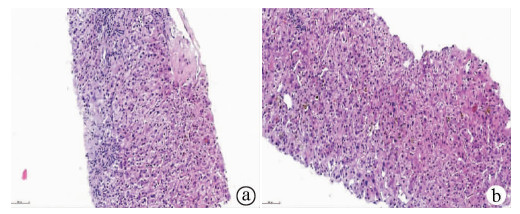

Hepatic alveolar echinococcosis misdiagnosed as intrahepatic cholangiocarcinoma: A case report

Kai ZHAO, Zhixin WANG, Shengbao WEN, Haijiu WANG, Haining FAN, Li REN

2021, 37(5): 1183-1185. DOI: 10.3969/j.issn.1001-5256.2021.05.042

Abstract(1037) HTML (359) PDF (2157KB)(63)

Abstract: